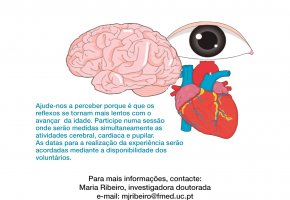

UC procura voluntários para estudo sobre o impacto do envelhecimento na função cerebral

Investigadores do Instituto de Imagem Biomédica e Ciências da Vida (IBILI) da Faculdade de Medicina da Universidade de Coimbra (FMUC) estão à procura de voluntários que queiram participar num estud...